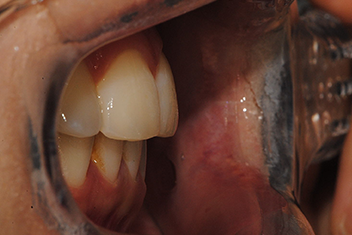

돌출입 개선

치료 기간20개월

상하악 돌출로 인한 돌출입을 투명교정으로 자연스럽게 개선